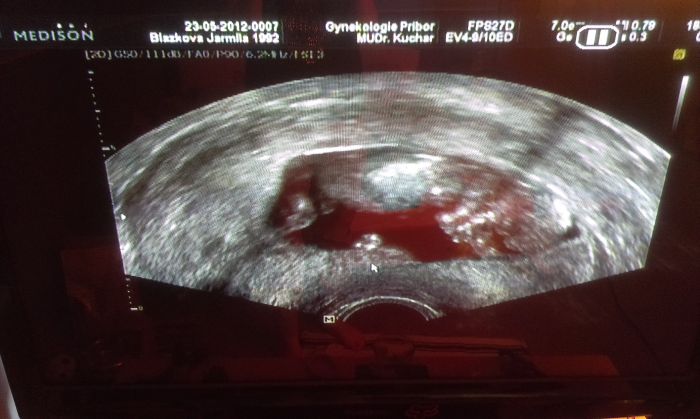

Ahojky, ja byla na kontrole a mela bych byt podle ms 9+2 , ale podle utz jsem 8+5, tak snad je vse v poradku, prcek ma 2cm, ale jsem z toho nejaka presla ani jsem se nestacila zeptat, jestli je to normalni.